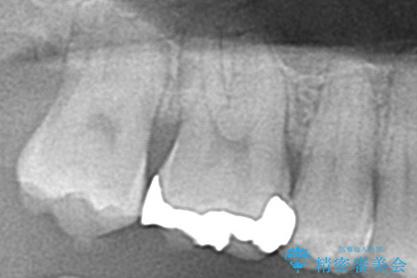

- 右上6番の銀歯をセラミックに変えたいと希望された患者様です。

切削量、形態を考慮し、セラミックインレーでの治療を計画しました。

銀歯と虫歯を除去した上でCRで裏層し形態を整えて印象を行っています。